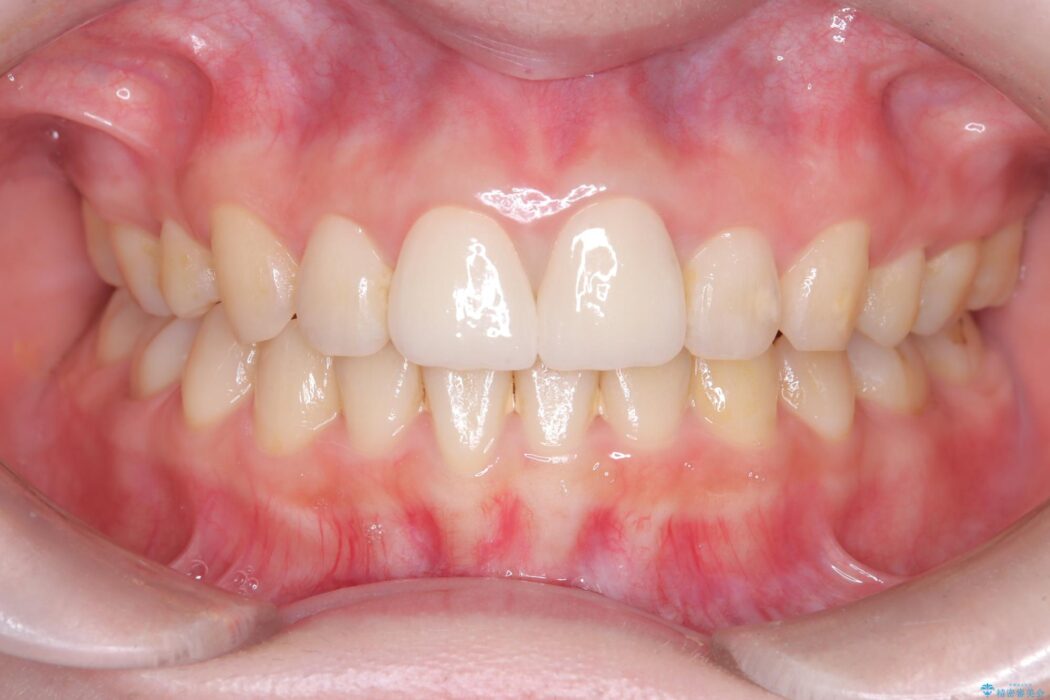

治療は、再感染の原因となっていた粗な根管充填材を丁寧に取り除く精密根管治療から開始しました。治療中はラバーダムと歯科用顕微鏡を使用し、根管内を徹底的に清掃・消毒。根の先まで緊密に薬を詰めることで、再発リスクを最小限に抑えました。根管治療の完了後、歯ぐきの状態を整え、周囲の歯と調和するオールセラミッククラウンを作製。金属を一切使わないため、透明感のある自然な仕上がりとなり、長年の見た目のコンプレックスも解消。歯の内部から表面までを根本的に改善することができました。